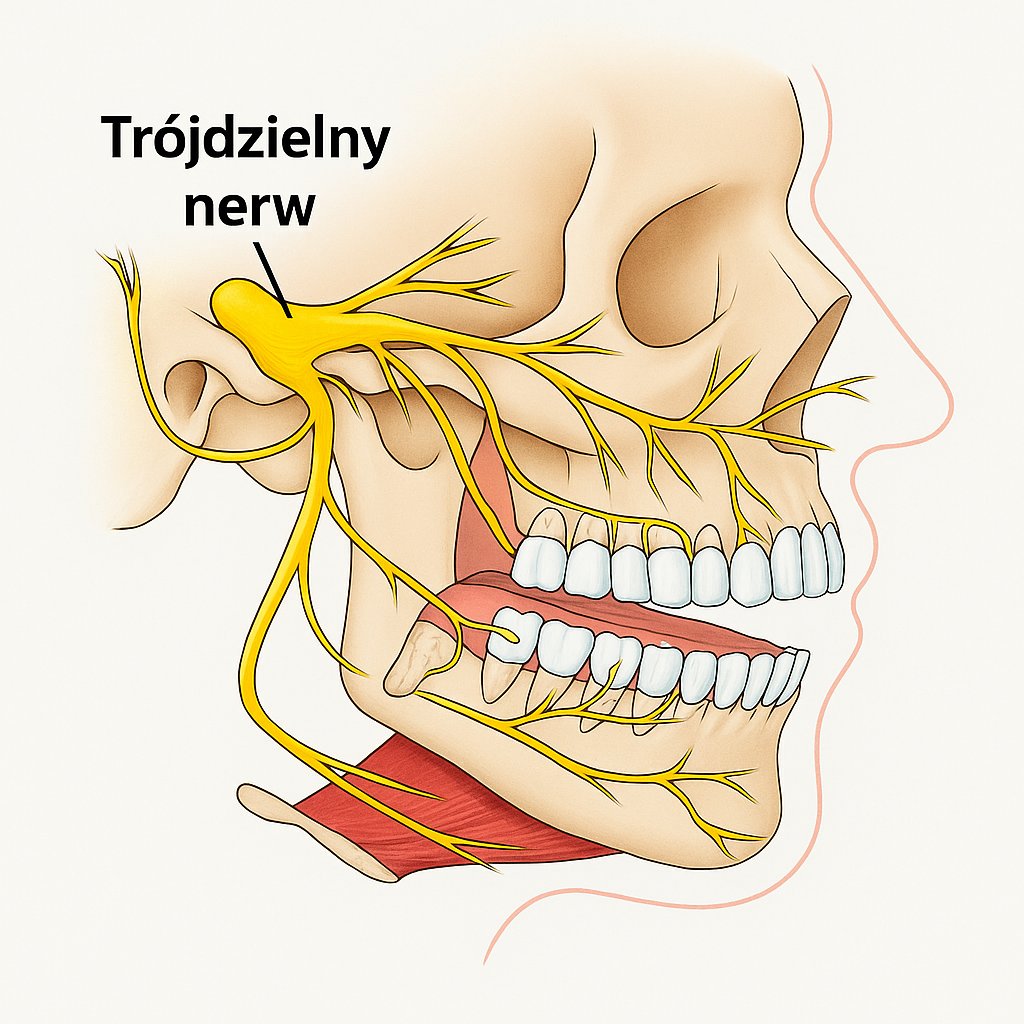

W żuchwie kość wokół zębów przednich i przedtrzonowców jest również cienka, dlatego infekcja najczęściej wychodzi do okolicy policzkowej (przedsionka jamy ustnej). Z tyłu natomiast blaszka językowa kości jest jeszcze cieńsza, a miejsce przyczepu mięśnia bródkowo-językowego znajduje się powyżej wierzchołków trzonowców. Dlatego stan zapalny często rozprzestrzenia się do przestrzeni podżuchwowej. Stamtąd infekcja może szerzyć się dalej – do tyłu i w dół, na szyję, a niekiedy nawet do klatki piersiowej.

Jeśli żyły znajdują się blisko ogniska infekcji, może rozwinąć się poważne powikłanie – zakrzepowe zapalenie żył (thrombophlebitis). Jest to stan zapalny ściany żyły z tworzeniem się zakrzepu. Najpierw stan zapalny obejmuje jedynie ściany naczynia (phlebitis), następnie przechodzi na otaczające tkanki (periphlebitis), a w końcu zajmuje całą żyłę. W wyniku tego przepływ krwi ulega spowolnieniu, skład krwi się zmienia, a jej krzepliwość wzrasta. Wszystko to sprzyja powstawaniu zakrzepów. W niektórych przypadkach mogą się one tworzyć nawet w zatokach żylnych mózgu.

Powikłania oponowe ropnia zęba (zapalenie opon mózgowych, ropień mózgu itp.) występują rzadko, jednak śmiertelność w tych przypadkach jest bardzo wysoka – od 40 do 90%. Takie schorzenia zwykle rozwijają się, gdy infekcja rozprzestrzenia się z ognisk pierwotnych – z okolicy skroniowej, dołu skrzydłowo-podniebiennego lub podskroniowego.